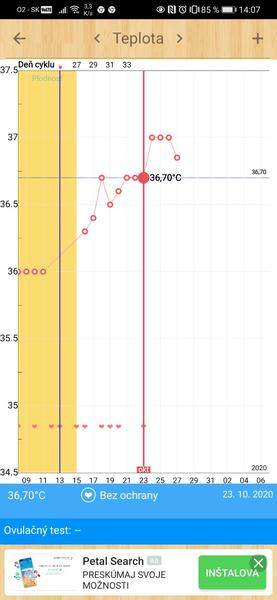

Grafy bazálnej teploty

Baby, nová téma o grafoch BT, ovulačných testoch, tehotenských testoch a hľadaní duchov je tu 🙂

Ak meriate bazálnu teplotu a zapisujete si hodnoty do grafov, ste na správnom mieste. Poradíme, pomôžeme, podporíme.

Grafy si môžete vytvárať na nasledovných stránkach:

www.fertilityfriend.com

www.womenzone.cz

www.wunschkinder.net

Všetko o meraní BT a jednotlivých programoch na vytváranie grafov nájdete tu: http://merenibt.xf.cz/index2.html